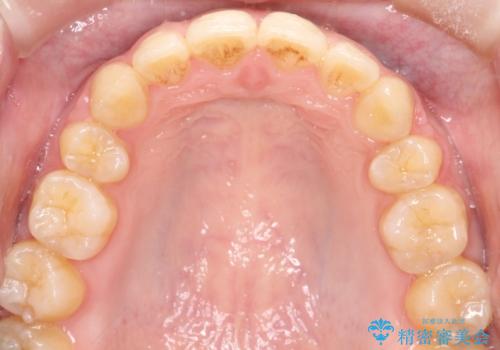

- 口元が出てるのが気になるとのことで来院されました。

歯のがたつきはあまりなかったのですが、口唇が閉じずらく、口元の突出感が確認できました。

上下左右の歯を1本ずつ抜歯して、そのスペースを利用して口元を引っ込める計画としました。

口元を下げて口唇を閉じやすくする場合、抜歯矯正をお勧めさせていただくことが多いです。